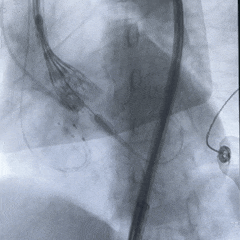

脱钩后造影,瓣膜位置可,几乎无瓣周漏

左冠切线造影,确认冠脉无遮挡

外周血管造影无损伤,手术结束